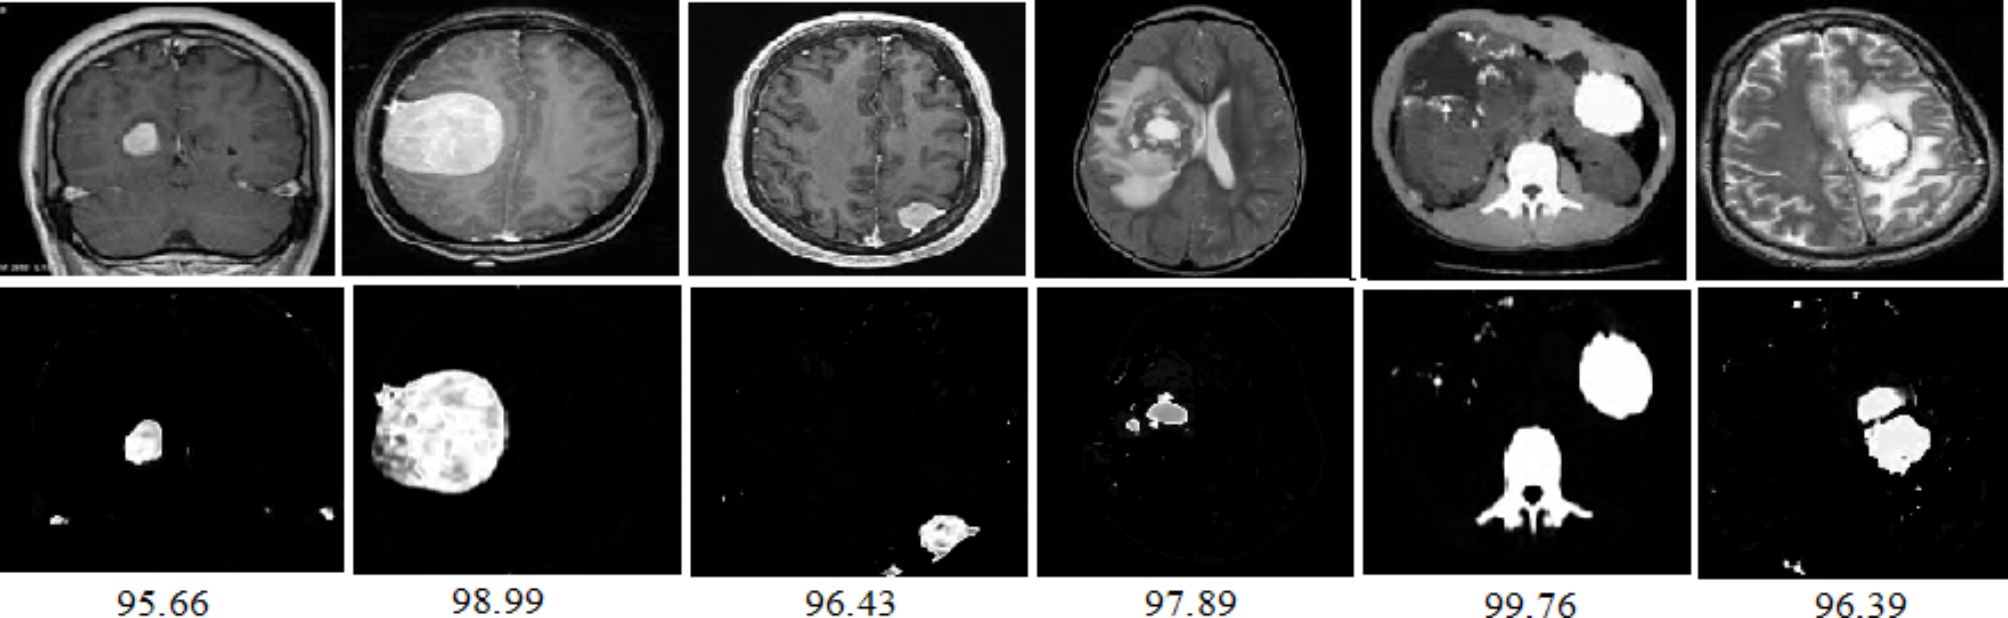

Segmentation of tumors with accuracies in MRI brain images for the proposed GKEIFCM method.